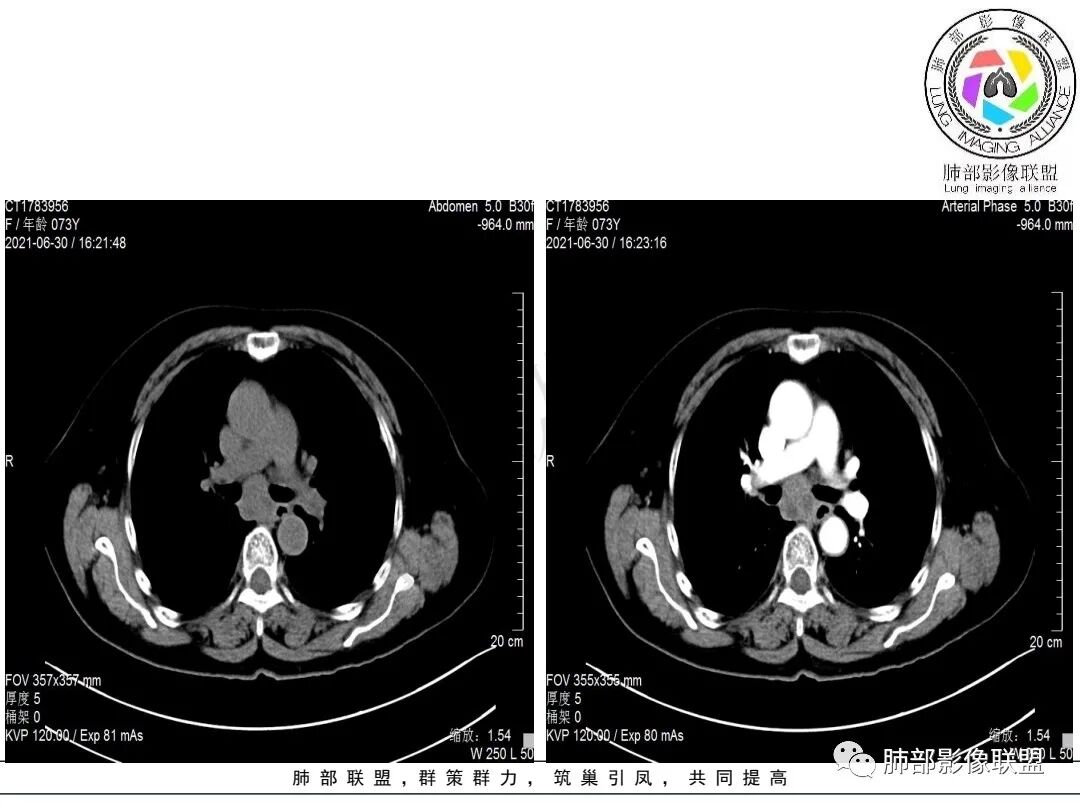

右肺下叶指套样高密度影,边界清楚,形态欠规则,累积多个叶段,平扫密度均匀,增强扫描不均匀强化,后纵隔淋巴结肿大,淋巴结内可见不均匀坏死,强化,女性,73岁,无实验室指标,考虑恶性:腺癌,鳞癌?神经内分泌癌(大细胞?),淋巴上皮瘤样癌。加一个转移瘤。

右肺下叶不规则形肿块,密度不均,轻度强化,纵隔肺门肿大淋巴结,里面血管好像破坏了,考虑恶性,鳞癌?鉴别结核。

右下肺肿块,多发浅分叶呈锯齿状,有指样突起和胸膜牵拉,不均匀强化,肿块内血管增粗模糊,后纵隔淋巴结肿大坏死融合呈冰冻状,定性恶性,低分化腺癌>小细胞肺癌。

老年女性,有桶状胸,长期吸烟?右肺下叶占位并纵膈7组,肺门10组淋巴结明显肿大融合,有不均匀性强化,肺内可见下叶支气管外压性狭窄,管腔近段感觉支气管没有影响,整体病灶成支气管走形,边界清楚,考虑恶性可能性大,小?

考虑小细,纵膈及右侧肺门淋巴结肿大并左下肺小叶间隔增厚,提示周围及中央淋巴管转移,左心房及左下肺静脉受累。

右肺下叶不规则肿块,纵隔及右侧肺门淋巴结肿大,不均匀强化,见坏死,考虑恶性,小细胞癌或鳞癌。

女,73,咳嗽2月。

胸部CT:桶胸,肺气肿背景,右下肺不规则肿块影,沿支气管血管束生长,边界较清,边缘毛糙、锯齿样,基底干支气管腔内隆起,部分支气管进入后堵塞。平扫密度较均匀,轻度强化,肿块内血管增粗模糊,7区淋巴结肿大明显,内见小片坏死,左房受侵,邻近胸膜增厚。考虑恶性,低分化腺?鳞?鉴别TB、PC等。

1.老年女性,咳嗽两月。CEA,T-spot阴性。

2.右肺下叶不规则实性密度块影,占据外后基底段及背段较大范围,可见轻度分叶、毛刺及棘状突起,未见明显胸膜牵拉及凹陷。

3.右肺下叶支气管轻度狭窄,病灶内见部分充气支气管征,外后基底段不能连续跟踪。

轻度不均匀强化,病灶内小血管显示不满意,未见明确坏死区。

4.右肺门及纵隔见多处增大淋巴结,不均匀环形强化,后下纵隔(隆突下)肿大淋巴结十分显眼!